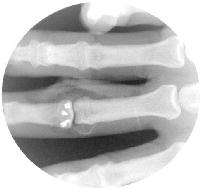

The pins are replaced with screws, one at a time. Here, two 1.3mm and one 1.0mm screws were used.

The last step before repairing the flexor tendon sheath is reattaching the volar plate. One method is to slightly back out the lateral screws, loop a suture from each corner of the volar plate around them, tighten and tie the suture, then advance the screws back in. The third screw provides extra security during this step.